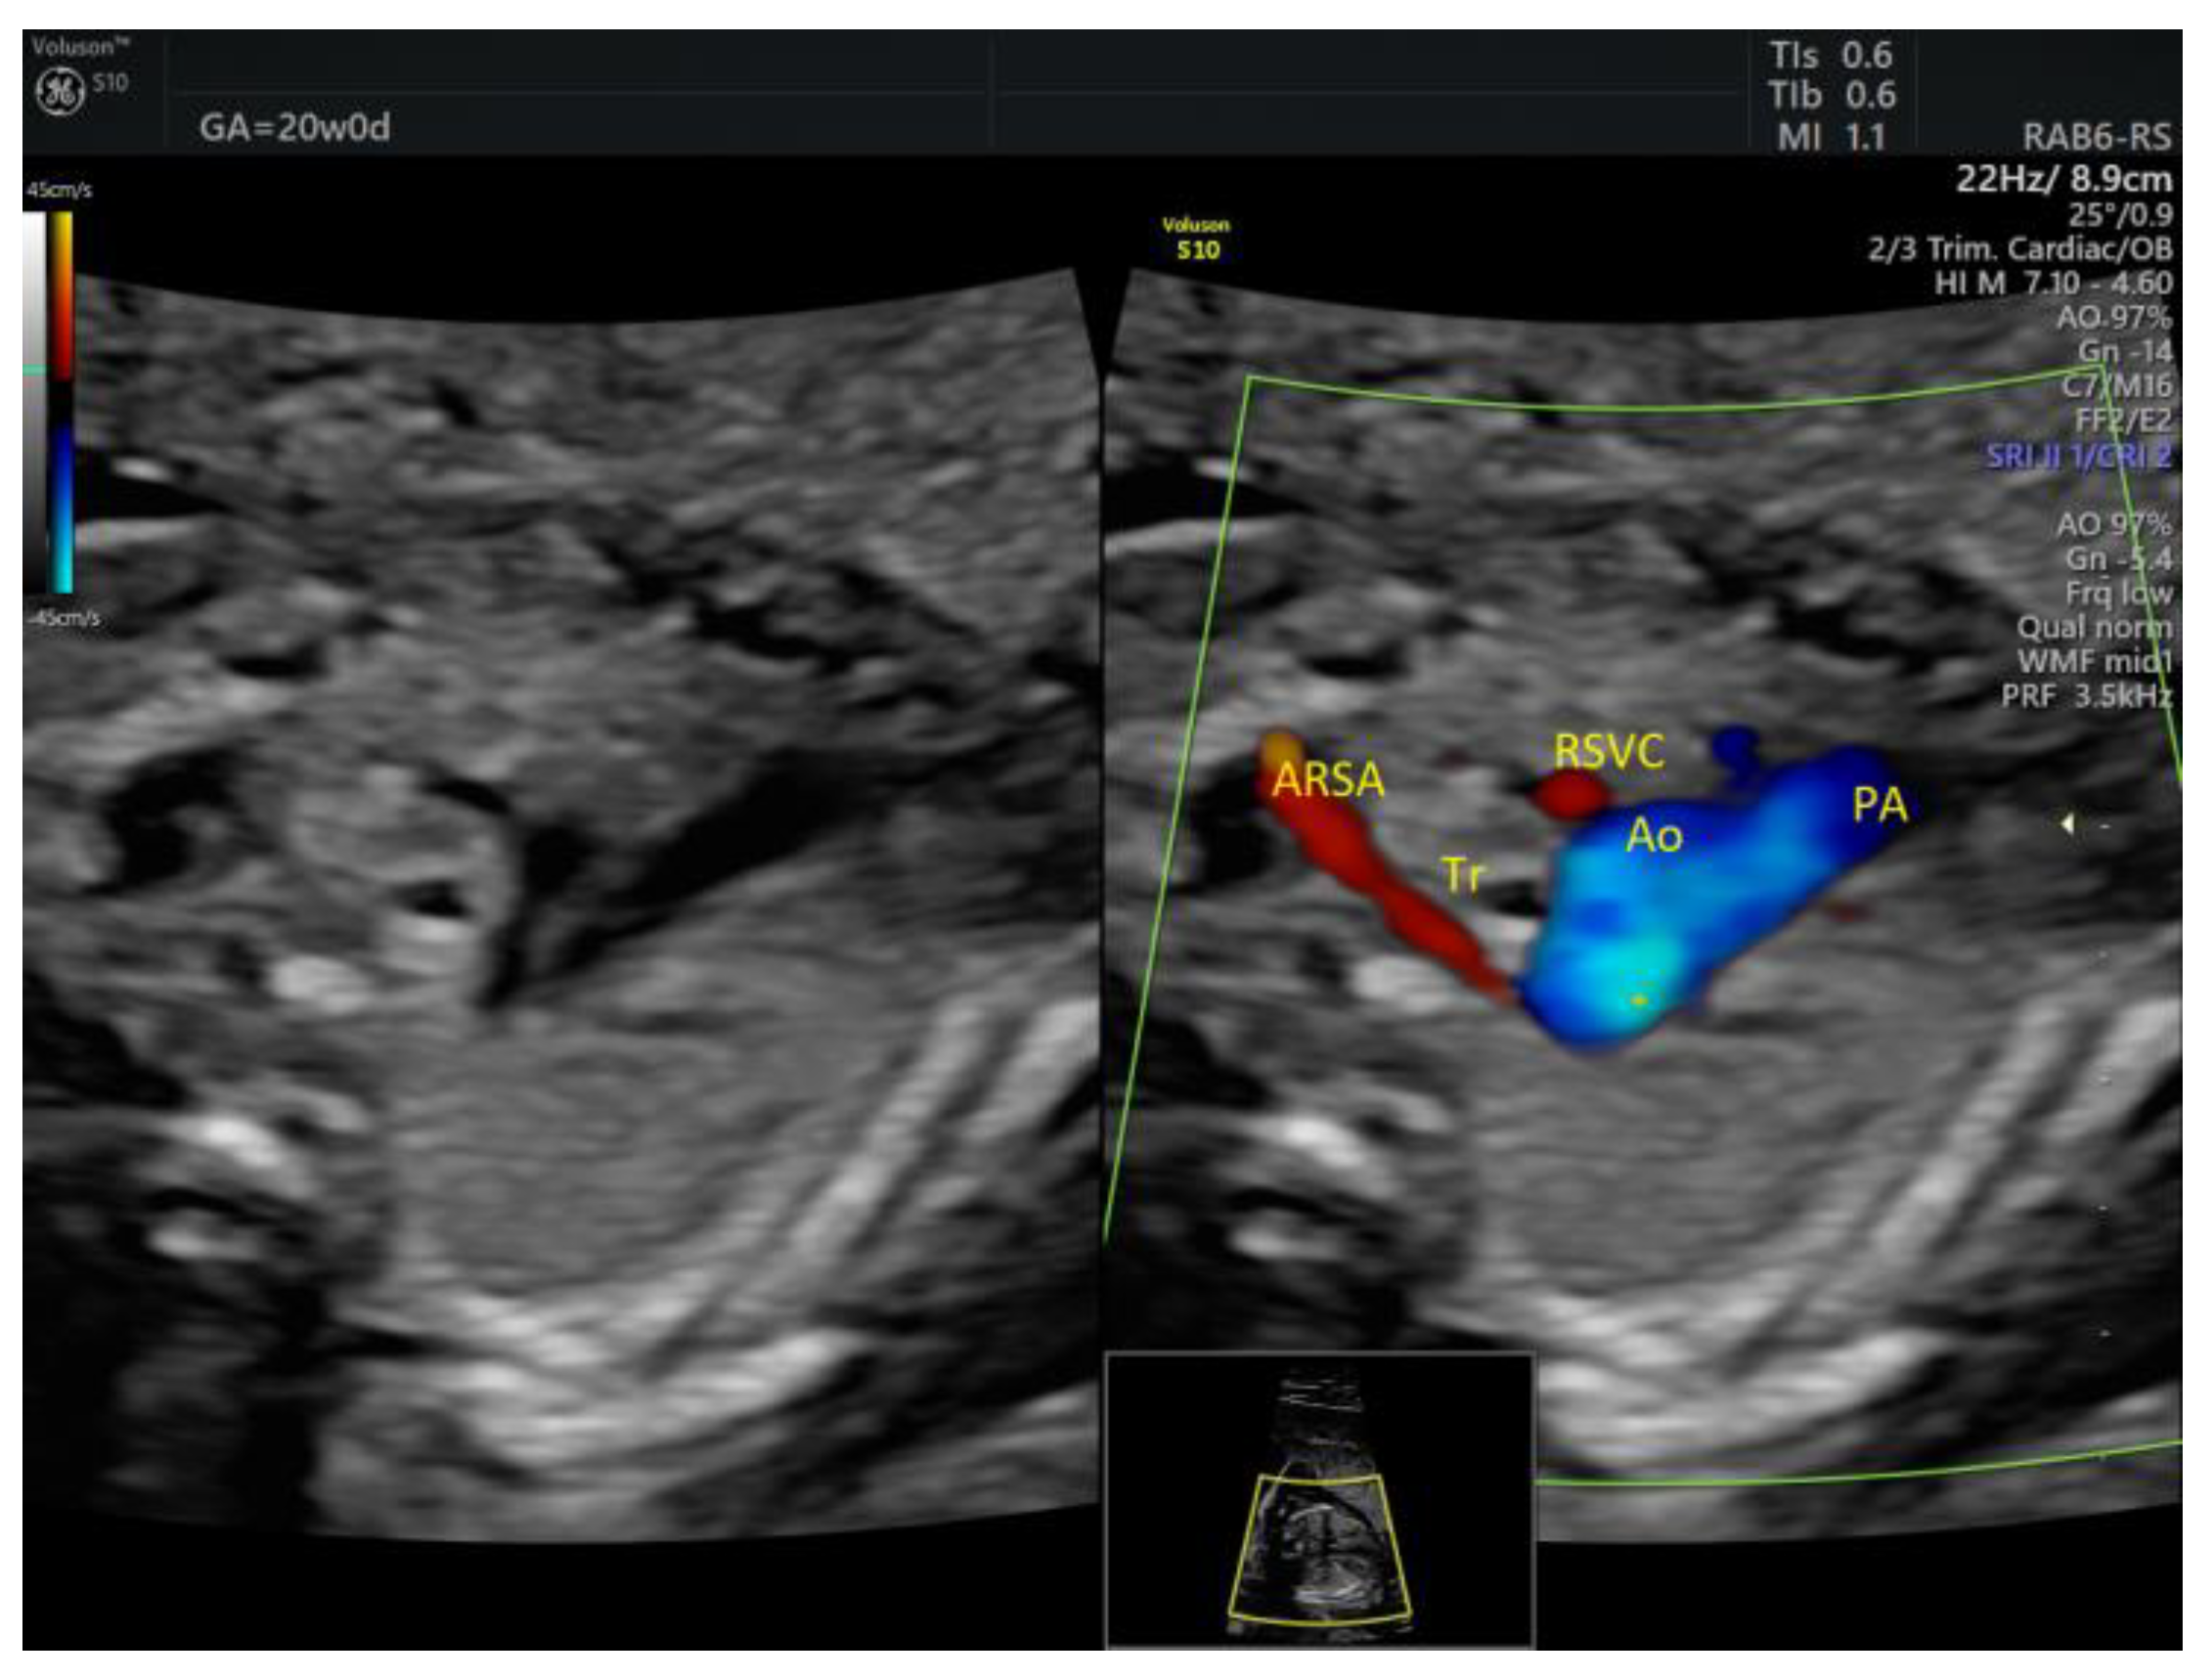

| Isolated ARSA | 6 | - | - | 3VT color | - | 0 | 6 | 0 | 2/5 |